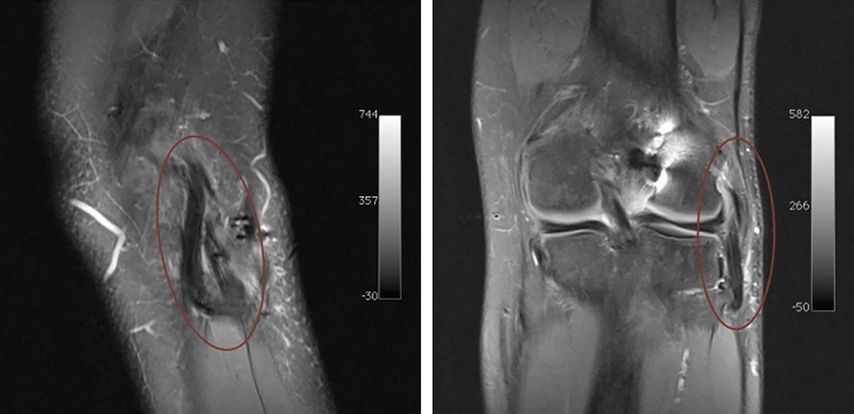

Aus unserer täglichen Praxis möchten wir den Fall eines 25-jährigen professionellen Fußballspielers vorstellen. Der Patient hatte sich während eines Spiels im Rahmen eines Hyperextensionstraumas eine vordere Kreuzbandruptur mit einer lateralen Seitenbandruptur zugezogen. Zusätzlich zeigten sich eine distale Partialruptur des M. biceps femoris und eine Teilruptur des M. popliteus (Abb.2). Die operative Versorgung erfolgte 14 Tage nach dem Trauma. Das vordere Kreuzband wurde mit einem BTB(Bone-Tendon-Bone-)Patellarsehnentransplantat, welches mit 2 Schrauben fixiert wurde, rekonstruiert. Intraoperativ zeigte sich, wie erwartet, eine vermehrte laterale Aufklappbarkeit unter Varusstress bei intakter Popliteussehne. Aufgrund der Begleitverletzung des M. biceps femoris wurde ein offener Zugang gewählt. Es wurde ein bogenförmiger lateraler Hautschnitt im Sinne einer „hockey stick incision“ angewandt und die laterale Gelenksecke sowie der N. peroneus dargestellt (Abb.3). Es zeigte sich die Sehne des M. biceps femoris am fibularen Ansatz handschuhförmig ausgerissen und das laterale Seitenband rupturiert. Es wurde die posterolaterale Gelenksecke mit einem Semitendinosustransplantat in Larson-Technik rekonstruiert und die Sehne des M. biceps femoris am fibularen Ansatz mit Fiberwire-Fäden transossär refixiert. Postoperativ wurde der Patient mit einer Knieorthese für 6 Wochen sowie Teilbelastung in den ersten 4 Wochen mobilisiert. In den ersten 2 Wochen erfolgte zusätzlich eine passive Mobilisierung mittels einer Motorschiene bis maximal 60°-Flexion.

Abb. 2: MRT des linken Kniegelenks eines 25-jährigen professionellen Fußballspielers nach Hyperextensionstrauma mit vorderer Kreuzbandruptur und Verletzung der posterolateralen Gelenksecke